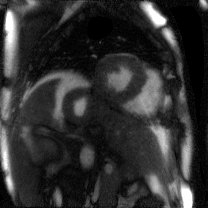

Supervised Deep-Learning (DL)-based reconstruction algorithms have shown state-of-the-art results for highly-undersampled dynamic Magnetic Resonance Imaging (MRI) reconstruction. However, the requirement of excessive high-quality ground-truth data hinders their applications due to the generalization problem. Recently, Implicit Neural Representation (INR) has appeared as a powerful DL-based tool for solving the inverse problem by characterizing the attributes of a signal as a continuous function of corresponding coordinates in an unsupervised manner. In this work, we proposed an INR-based method to improve dynamic MRI reconstruction from highly undersampled k-space data, which only takes spatiotemporal coordinates as inputs. Specifically, the proposed INR represents the dynamic MRI images as an implicit function and encodes them into neural networks. The weights of the network are learned from sparsely-acquired (k, t)-space data itself only, without external training datasets or prior images. Benefiting from the strong implicit continuity regularization of INR together with explicit regularization for low-rankness and sparsity, our proposed method outperforms the compared scan-specific methods at various acceleration factors. E.g., experiments on retrospective cardiac cine datasets show an improvement of 5.5 ~ 7.1 dB in PSNR for extremely high accelerations (up to 41.6-fold). The high-quality and inner continuity of the images provided by INR has great potential to further improve the spatiotemporal resolution of dynamic MRI, without the need of any training data.

翻译:在这项工作中,我们建议了一种基于IRI的方法,用这种方法来改进动态磁共振感应成像(MRI)重建,而该方法只是以高度低劣的 k-空间数据为基础,而该数据仅以磁共振坐标作为投入。具体地说,拟议的IRI将动态MRI图像作为一种隐含功能来表示,并将其编码到神经网络中。网络的权重仅从稀有的(k, t)空间数据本身中学习,而没有外部培训数据集或先前的图像。 利用基于IRI的强有力隐含性稳定化,同时不以清晰的动态和时空坐标坐标坐标坐标坐标作为投入。 拟议的IRIR将动态MRI图像作为一种隐含功能,将其编码到神经网络中。网络的权重仅从淡化的(k, t)空间数据本身学习,而没有外部培训数据集或先前的图像。